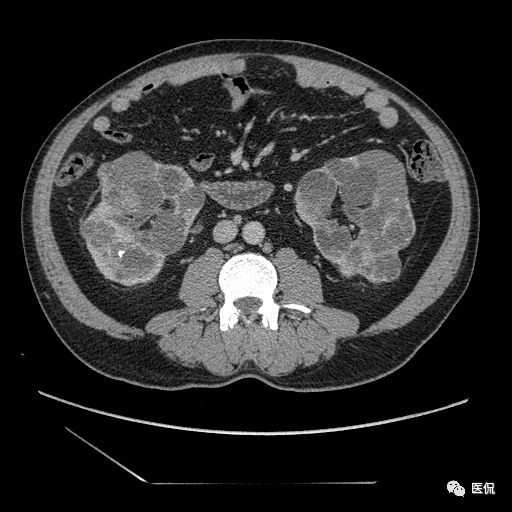

双肾实质可见多发囊性密度灶,其内密度不均匀,并可见钙化灶,增强扫描未见明显强化灶。肾周脂肪间隙清晰,与邻近组织分界清楚。

多囊肾的 CT 表现主要表现为双肾增大,轮廓光滑或有分叶,肾实质内多个大小不等的囊肿呈蜂窝状,多呈水样低密度,增强扫描囊肿本身无强化,而囊肿间正常肾组织增强,对比明显。当囊肿张力过高,使囊壁上毛细血管牵拉破裂出血时,表现为囊肿内稍高密度影,随访CT 值减低。囊壁钙化,表现为点线状高密度影像,随访CT值无变化。有文献报道约 30%病例可并发多囊肝或多囊胰。